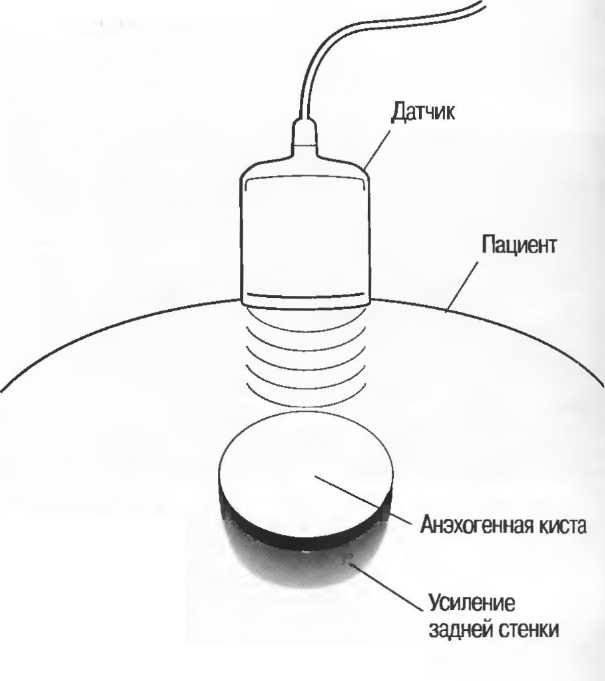

Кисты

Киста, как правило, визуализируется в виде анэхогенной зоны, при этом структуры, расположенные за кистой, обычно усилены: полость кисты анэхогенна, поскольку в ней нет структур с различным акустическим сопротивлением. В результате того что жидкость не поглощает ультразвук в такой же степени, что и ткань, эхо-сигналы от расположенных позади кисты структур гиперкомпенсированы сканером и выглядят усиленными — появляется эффект усиления задней стенки (рис. 14а,б).

Киста определяется в виде анэхогенной зоны с усилением по задней стенке. Если в кисте есть внутренние зхоструктуры, то они могут быть реальными или являться артефактами.

Рис. 14а. Заполненная жидкостью киста: полость кисты анзхогенна, имеется усиление задней стенки.

Структура, наподобие содержащей чистую жидкость кисты, визуализируется как анэхогенная зона. Стенки кисты отражают ультразвуковые сигналы под углом, и информация не поступает назад в трансдьюсер. В результате этого появляются боковые тени, но сзади кисты имеется усиление эхосигналов (усиление задней стенки) (рис. 15).